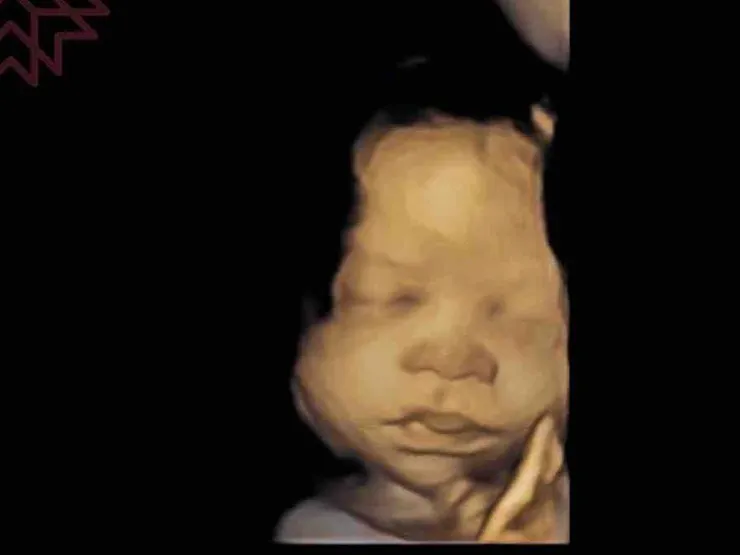

話說回來,這超音波清楚到連醫師都讚嘆不已,而且是兩個都照得到,有種提前開獎的感覺,妳們好呀!

35+5,成長速度同步的同卵雙胞胎,雖然乖到醫師一直冒小花,但真的苦了媽咪的肚子,2900 x 2可是5800啊!!